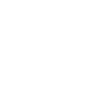

خبرني - تمكن علماء يابانيون من إيجاد طريقة قد تساهم في إبطاء شيخوخة القلب، بل وحتى استعادة بعض وظائفه التي تتأثر مع التقدم بالعمر.

وقال العالم:"تبين النتائج التي توصلنا إليها أن الميتروبين يساهم في إبطاء شيخوخة الخلايا المرتبطة بالتقدم بالعمر، بما في ذلك خلايا القلب، ما يؤدي إلى تحسين الوظائف القلبية".

وشدد العالم على ضرورة إجراء المزيد من التجارب للتأكد مما إذا كان التأثير نفسه يحدث لدى البشر، مشيرا إلى أن تراجع وظيفة الميتوكوندريا هو أساس العديد من الأمراض المرتبطة بالشيخوخة، وأن نجاح هذه الأبحاث قد يؤدي إلى تطوير استراتيجيات علاجية جديدة للشيخوخة.